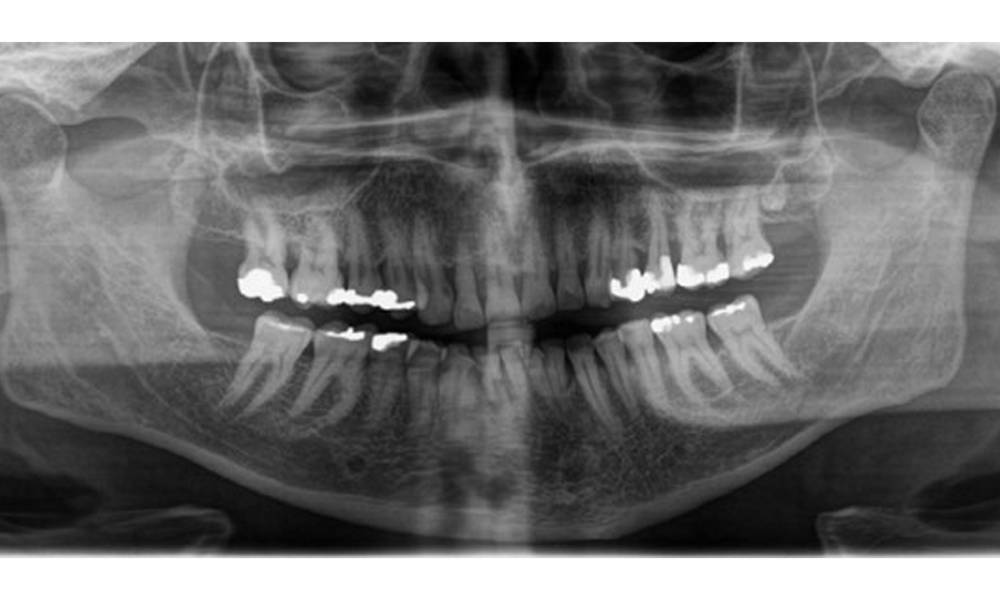

Рентгенологични резултати

Налице е пълно съзъбие на възрастен човек с генерализирана костна загуба между 20-50% и множество зони на вертикална костна загуба. Рентгенологичното изследване не разкрива видими кариозни лезии. (Фиг. 7)

Панорамна рентгенова снимка, показваща генерализирана радиологична загуба на кост с множество вертикални дефекти между 20 и 50 %.

Фиг. 7 Панорамна рентгенова снимка, показваща генерализирана радиологична загуба на кост с множество вертикални дефекти между 20 и 50 %. © д-р Р. Крапф